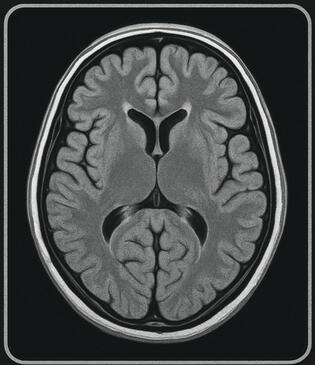

Ending the 5–7 year wait for rare pediatric epilepsy diagnosis Below that (body): Privacy-first AI that detects Dravet, tuberous sclerosis, and Sturge-Weber from routine MRI/CT in under 30 seconds.